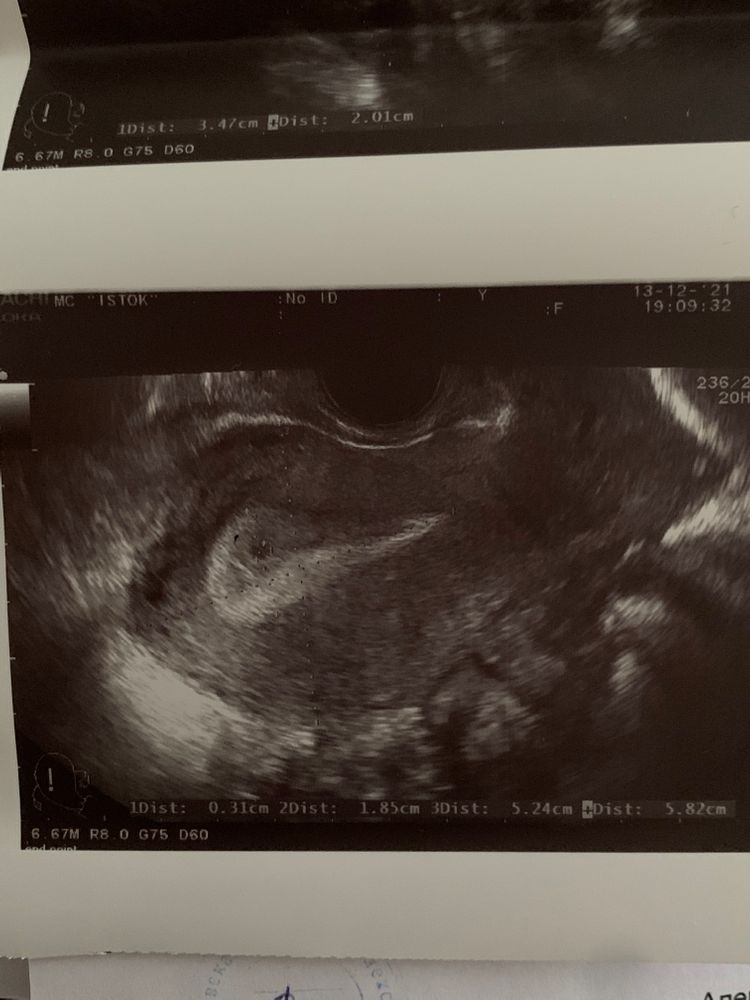

Tatyana, да, уже думаю, что ХГЧ точно покажет. Мне просто непонятно, что в матке есть «округлое образование размером до 2мм» и Б не исключена.

Tatyana, благодарю 🙏🏻 мне сейчас как никогда нужна поддержка! Муж тоже говорит, чтобы я не волновалась! Но это так долго , целых 10 дней ждать. на вопрос врачу, почему тесты не показывали, она ответила, что ещё очень рано для этого. Бусинка ещё крошечная🥺 но я надеюсь и верю в лучшее!!!